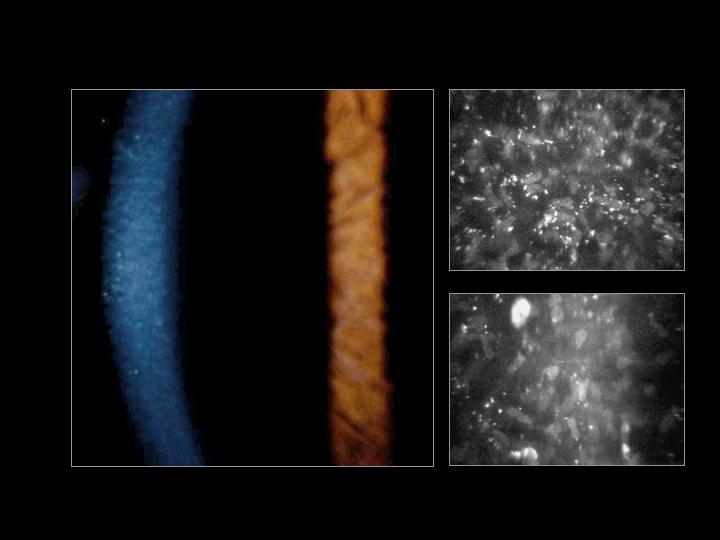

문자그대로 주근깨와 같은 작은 혼탁이 기질에만 존재하는 질환입니다.

작은 혼탁이 상피는 침범하지 않으며, 기질의 전층에 발생합니다.

미세한 회색 얼룩이 양측 각막의 전층에 발생하게되며,